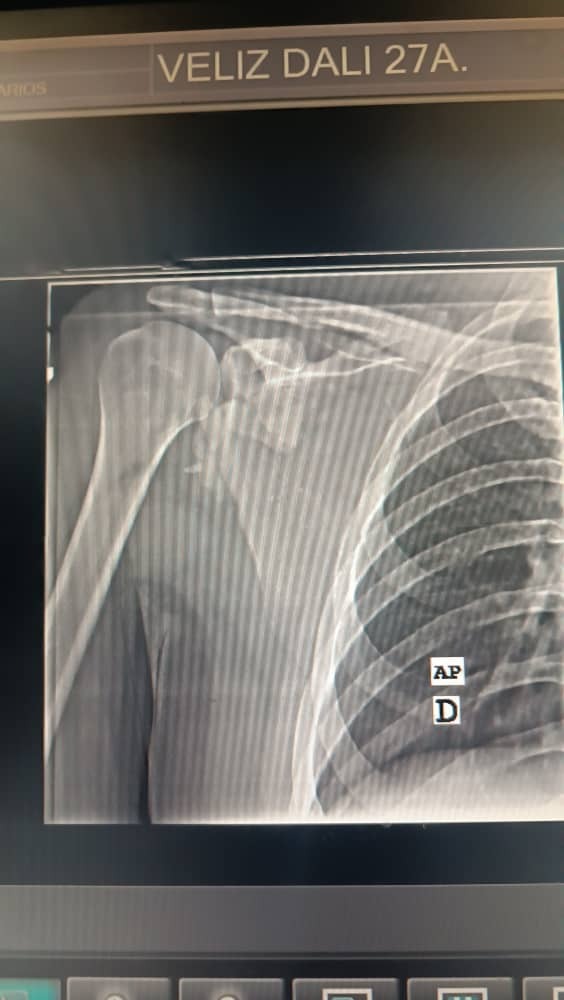

Mi nombre es Dalí Leonardo Véliz Fernandez, y hoy les pido su apoyo en un momento increíblemente difícil. Recientemente, el pasado lunes 30 de junio de 2025 sufrí un grave accidente automovilístico en la Autopista Regional del Centro (ARC), justo cuando regresaba a Caracas de un viaje de trabajo durante el fin de semana. El impacto fue severo y, lamentablemente, resultó en una gran fractura de escápula en mi hombro derecho.

Esta lesión no es solo dolorosa, sino que me impide realizar incluso las tareas más básicas y amenaza mi capacidad para volver a mi vida normal. Para poder recuperarme por completo, necesito someterme a una cirugía urgente y compleja. El presupuesto estimado para esta intervención, junto con los tratamientos post-operatorios, asciende a $17.000. Es una suma considerable que, sin su ayuda, sería imposible de cubrir.